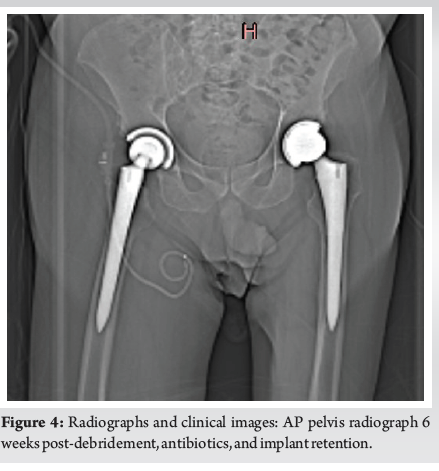

Short-term Success in Treatment of an Acute Hematogenous Periprosthetic Hip Joint Infection with Debridement, Antibiotics, and Implant Retention

Senah E. Stephens , Cody L. Evans ………………………………p.47-52